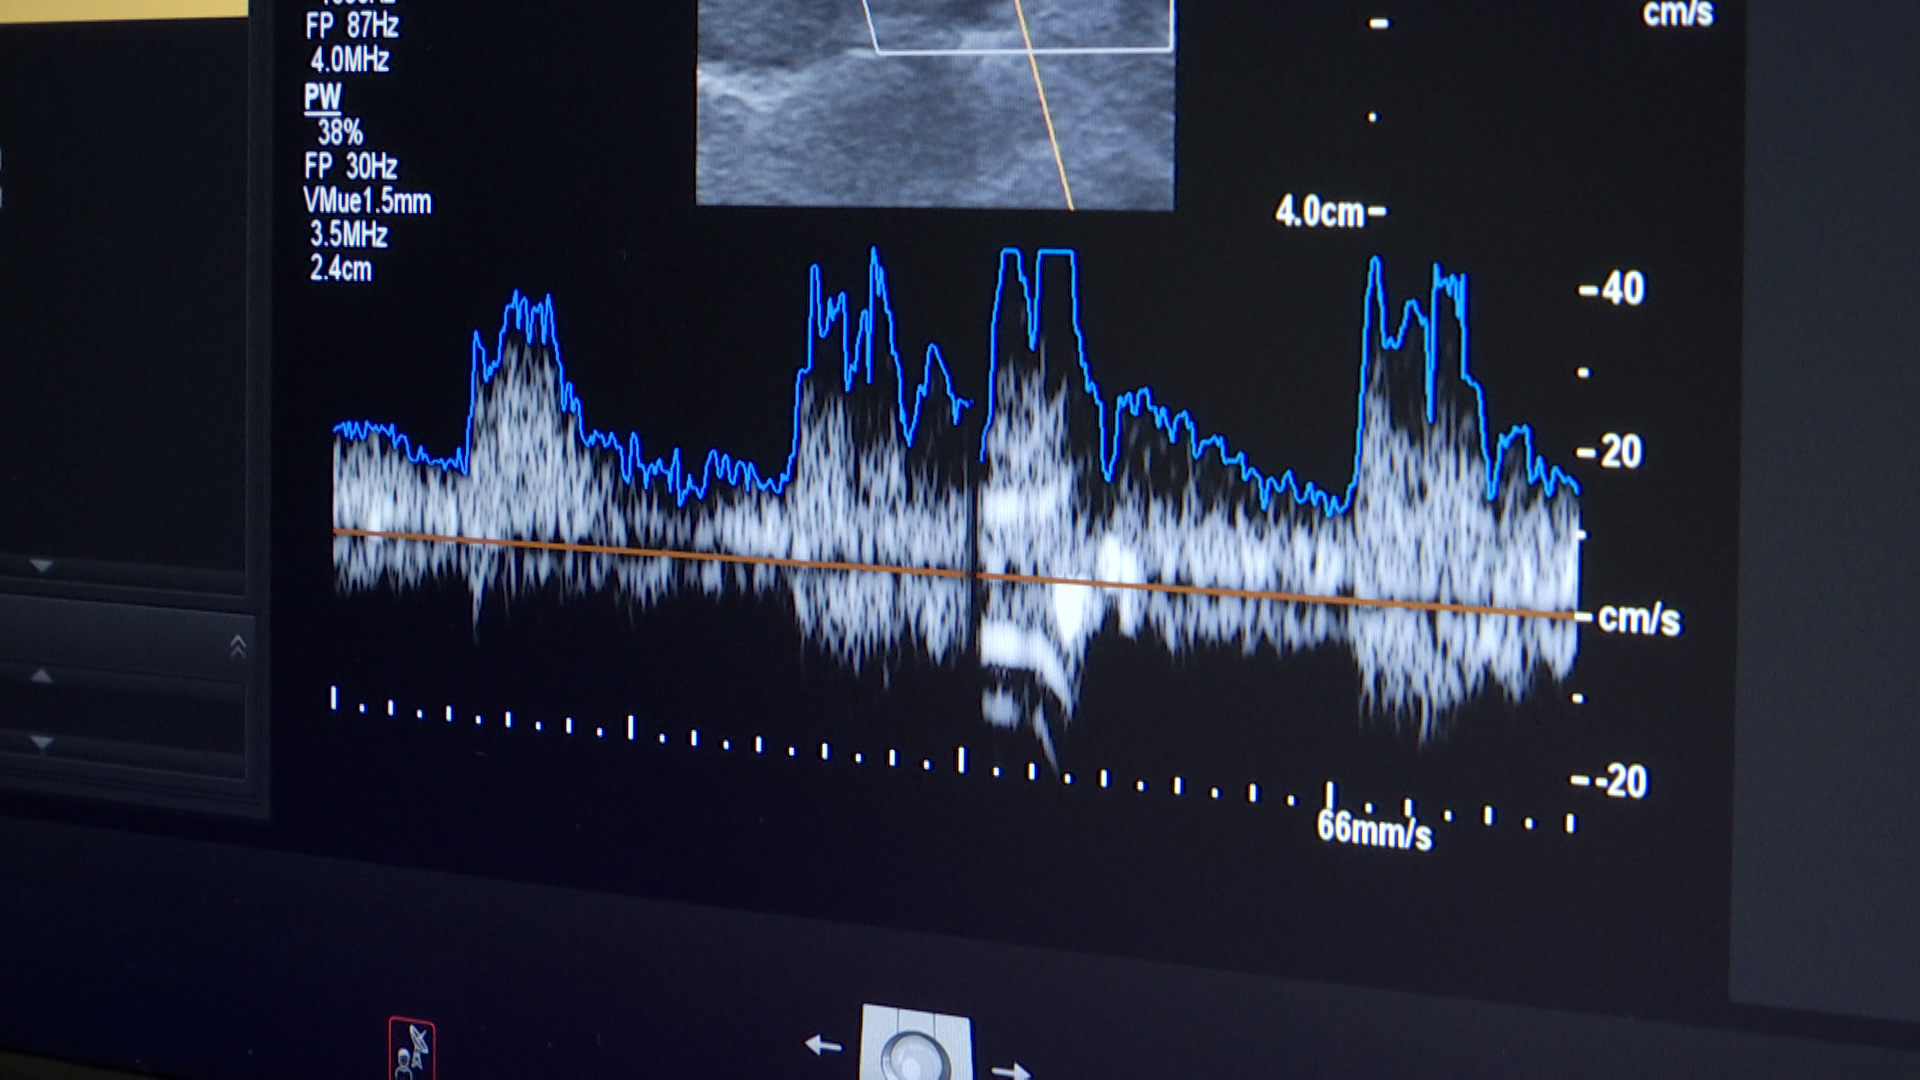

Durant la jornada, organitzada per la Unitat d’Ictus de l’Hospital, s’han fet controls de pressió arterial i glucèmia, i s’han donat consells sobre hàbits de vida saludables. Els participants amb més de dos factors de risc, com la hipertensió, fumar o problemes cardiovasculars, han pogut fer-se una ecografia de les caròtides per comprovar el flux de sang al cervell.

Entre els participants hi havia la Carme Moreno, usuària de l’hospital, que ha volgut aprofitar l’activitat per fer-se una revisió. “Jo, com que tinc colesterol i soc hipertensa, m’han dit si em volia fer una ecografia per mirar-me la caròtida, per si tenia risc d’ictus. He pensat que era molt important i molt interessant, i m’han fet una ecografia”, ha explicat.